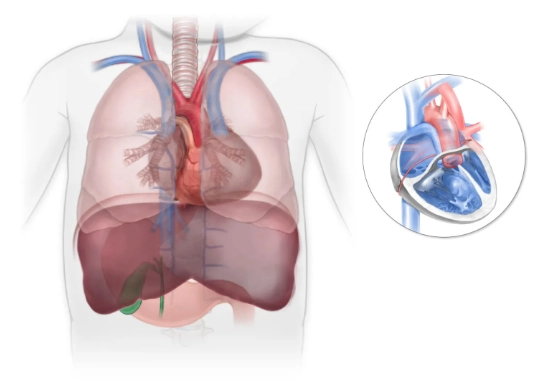

Nang lách (Splenic Cyst)

U máu lách (Splenic hemangioma)

U mạch bạch huyết lách (Splenic lymphangioma)

Lymphoma lách (Splenic lymphoma)

Hamartoma lách (Splenic hamartoma)

U mạch máu ác tính lách (Splenic angiosarcoma)

Di căn lách (Splenic metastases)

Tạo máu ngoài tủy tại lách (Extramedullary hematopoiesis in the spleen)